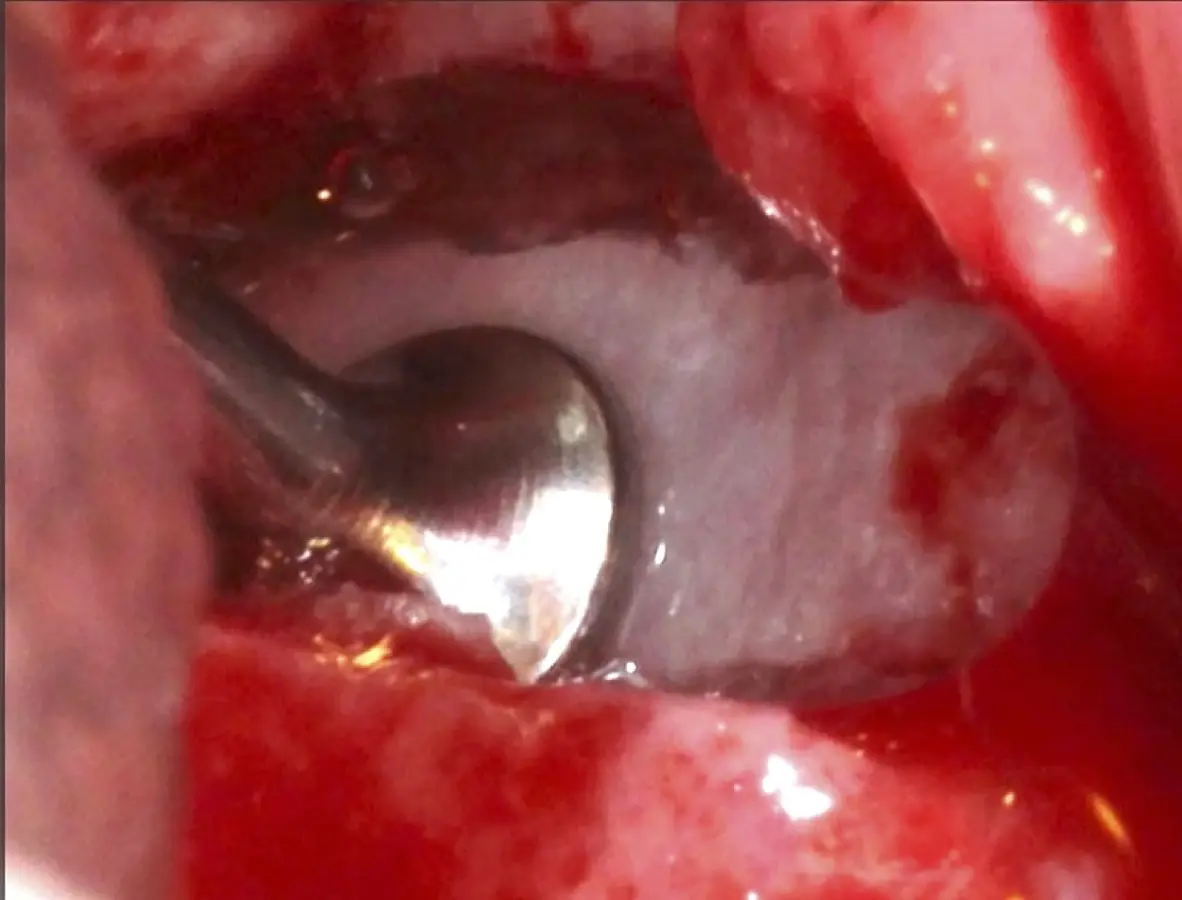

La técnica se inicia con la colocación de anestesia infiltrativa, posteriormente se realiza una incisión crestal o paracrestal con posibles liberantes verticales que deben de estar alejadas por lo menos 5 mm de los límites de la futura ventana y sobrepasar la línea mucogingival. Se realiza una elevación de colgajo, se inicia la antrostomía y antroplastía. Para ello, se emplea el inserto redondo diamantado de corte al momento de delimitar los bordes de la ventana de acceso. Luego se cambia al inserto aserrado liso de calibre fino con superficie diamantada, para profundizar y eliminar el hueso en el contorno de la ventana. Una vez que se traslucen los tejidos, se puede optar por el retiro de la tapa ósea o el levantamiento de ésta junto con la membrana.

Se inicia la elevación de la membrana de Schneider con el inserto redondeado no cortante en forma de disco, empleando movimientos suaves. El levantamiento puede complementarse con elevadores convencionales, siguiendo la dirección mesiodistal. La fase de desprendimiento inicia con el piso y sigue hacia la pared mesial para terminar, y de ser necesario, hacia la pared posterior. Existen diversos insertos con angulaciones y longitudes para mayor accesibilidad16 (Figura 1).

El tipo de inserto a ser utilizado dependerá del espesor de la pared ósea. Si la pared es menor a 0.5 mm, es mejor utilizar insertos de desgaste para prevenir la ruptura de la membrana de Schneider; si el espesor es mayor a 0.5 mm, se puede utilizar insertos de corte de espesor medio (Figura 3).